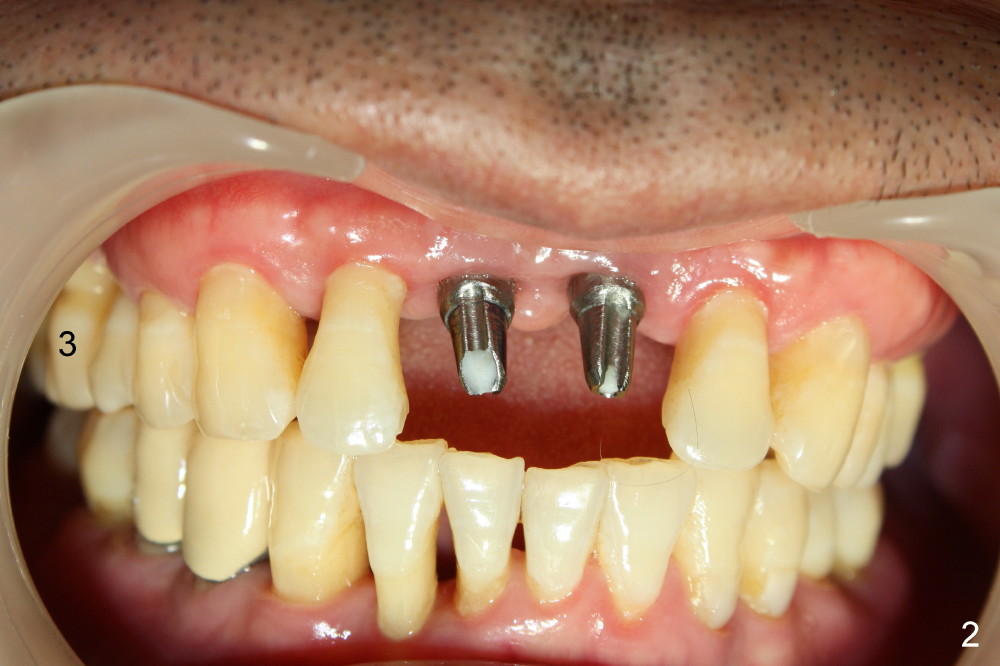

Today the tooth #3 was extracted because of cold sensitivity and immediate implant placed (Fig.3: 7x17 mm).  This is my plan.  Four months later, a 6 mm 0 degree unipost will be rotated in place tightly without cementation.  One or two heavy antirotational grooves will be placed between the implant and the abutment.  A temporary or permanent crown will be cemented temporarily.  In case, a hybrid denture is expected in the future.  The crown and the abutment can be removed easily.